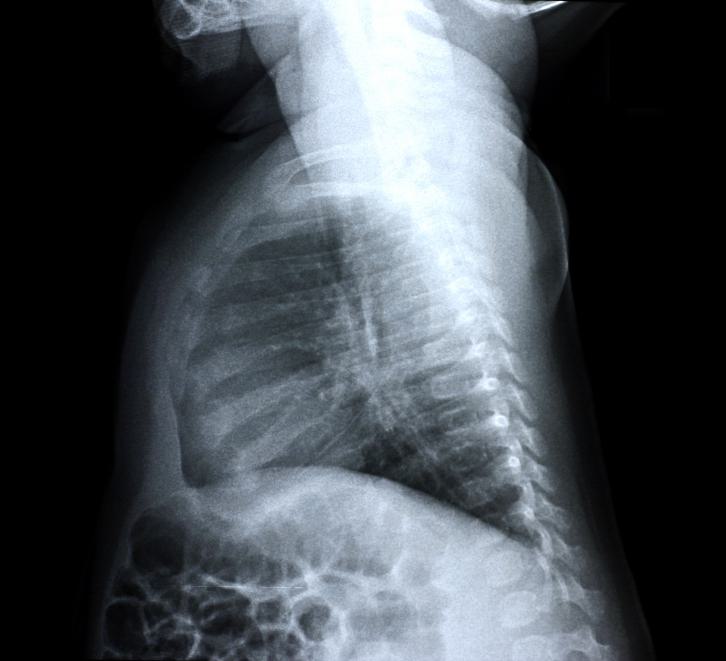

The brachial plexus is made up of five nerves between the neck and arms that carry messages and provide movement from the brain and spinal cord to the muscles of the shoulders, arms, and hands. Shoulder dystocia can occur during a delivery when the baby’s shoulder is impacted on the mother’s pelvis after the delivery of the baby’s head. Risk factors include gestational diabetes, excessive maternal weight gain during pregnancy and a larger than normal baby. An injury can occur if excessive force (traction) is employed to deliver the shoulder rather than employing the appropriate obstetrical manuevers, or if the child is too large to be delivered vaginally. Some babies become so large (macrosomic) that it is safer to deliver them by Caesarean section. A brachial plexus injury can be mild, where the nerves are only stretched and bruised, and can heal over the course of several months. However, this injury can also be severe, requiring surgery and resulting in ongoing paralysis to the baby’s arm, neck, and shoulder, known as brachial plexus palsy.